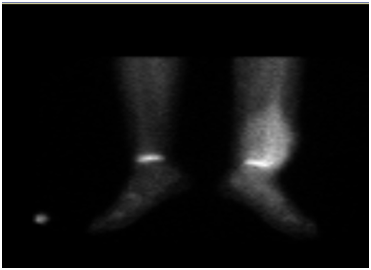

A girl, 11yearsold Saudi presented to us with progressive swelling of the left lower limb, localized above the left ankle with complaints of pain and limping gait. She had visited many clinics for her pain and swelling with no relief to her symptoms. The patient was examined clinically and there was a swelling in the lateral aspect of the distal leg tender firm too hard with intact skin over it, 4x3 cm, no other systemic clinical finding of note. X-ray of the left leg (Figure 1) showed aggressive lytic lesion of the distal fibula. Thence patient was investigated with basic lab works plus systemic and local staging for further diagnosis. She was admitted under us in pediatric surgical ward for open biopsy of the distal fibular lesion and CT of the lower limb (Figure 2) showed destructive bone lesion involving the distal end of the fibula associated with extensive destruction and aggressive periosteal reaction associated with large soft tissue mass 4.5 x 5 cm in maximum axial dimension. Also, MRI of the lower limb (Figure 3) showed there is a large destructive bone lesion involving the distal diaphysis of the left fibula. This lesion does not cross the growth plate. It is associated with aggressive periosteal reaction along with a large soft tissue mass that appears of high signal intensity in T2 and intermediate to low signal intensity in T1 sequences. This was followed by technetium-99m MDP scintigraphy (Figure 4), it showed an increased tracer uptake in the distal left fibula, extending to the left ankle and the left foot. Excisional biopsy was taken from the proximal and distal margin of the lesion in the left fibula which confirmed Ewing's Sarcoma. According to the histopathology department, they reported that there is no evidence of residual tumor i.e free resection margins. (Figure 5) The patient was referred from us to pediatric oncology clinic for further evaluation. She was electively admitted to the hospital for staging and central line insertion to start chemotherapy. She treated as per Ewing sarcoma protocol in our hospital. Patient was put on neoadjuvant chemotherapy which included vincristine, cyclophosphamide, doxorubicin and etoposide, and if osfamide 3 times weekly. After 6 months of chemotherapy, we recommend to her family to do a surgery. We did a wide surgical resection of the tumor in the left leg. Subcutaneous tissue was dissected and isolation of superficial peroneal nerve was done. Dissection of lateral compartment of the left leg up to 16cm proximal to the lateral malleolus and distally, until the distal physis (Figure 6). The tendons of the peroneus longus, peroneus brevis, and flexor halluces longus were sacrificed and the ruminants were used to reconstruct for the lateral aspect of the left ankle using suture anchors (Figure 7). K-wires were used to do temporary arthrodesis (Figure 8). The surgical wound was closed in layers. VAC dressing was also applied as standard care management in Oncology cases at KFMC and backs lab was applied (Figure 9). The last MRI done for the patient showed there is altered signal intensity of the soft tissue with post-contrast enhancement. However, the dimensions of this area of altered signal intensity are decreased as compared to previous MRI. There is no evidence of soft tissue mass lesion (Figure 10). According to the last patient's follow up after six months post-operation it shows no Valgus deviation, normal ankle motion, mobilizing full weight bearing with splint assistant during physical examination (Figure 11). Also, X-rays and MRI finding shows no residual mass lesion or local recurrence.

Figure 4 Bone scintigraphy demonstrates an increased tracer uptake in the distal left fibula, extending to the left ankle and the left foot.

A Saudi girl, 10 years old presented to OPD with progressive swelling of the right ankle for 3 months, localized on the lateral aspect, and increasing with pain and swelling within last two months. During physical examination, proximal area of the skin over the swelling was dark black as what was noted. The patient was investigated primarily in a hospital outside of Riyadh according to a biopsy was taken with osteomyelitis of distal fibula and treatment was start taken but with no response. X-ray of the right leg (Figure 12) and CT of the lower limb (Figure 13). An expansile, lytic and destructive bone lesion is seen involving the distal third of the right fibula. (Figure 14) on MRI showed there is a large destructive bone lesion involving the distal third of the right fibula with sparing of the distal fibular epiphysis. No definite involvement of the right tibia and talus. Trace of fluid is seen in the right tibiotalar joint most likely reactive. The neurovascular structures appear intact. This was followed by technetium-99m MDP scintigraphy (Figure 15), what it showed a solitary focal lesion distal end of right fibula compatible with suspected Ewing's sarcoma. No additional lesions were noted to suggest skip lesions or metastasis. She treated as per Ewing sarcoma protocol in our hospital. Patient was put on neoadjuvant chemotherapy. Later, We did a wide surgical resection of the tumor was preformed upto12 cm from the distal fibula malleolus during which ,the superficial peroneal nerve and peroneus longus and brevis tendon were sacrificed the ruminant of the peroneus longus and calcaneo fibular ligament were sutured and using anchors were attached to the distal tibia in the right leg free pedicle latissmuss dorsi flap was anastomosed to the peroneal artery locally to cover the soft tissue defect by the plastic surgery team. The last MRI done for the patient (Figure 16) showed there is interval reduction in the size of the previously noted heterogeneous enhancing mass at the distal metaphysis of the right fibula. On the bone scan (Figure 17), there is interval reduction in the size of the previously noted heterogeneous enhancing mass at the distal metaphysis of the right fibula. There is no sign of skip metastases to other limb. Bilaterally bone marrow signal changes are most likely related to chemotherapy. The patient will follow up with us regularly.